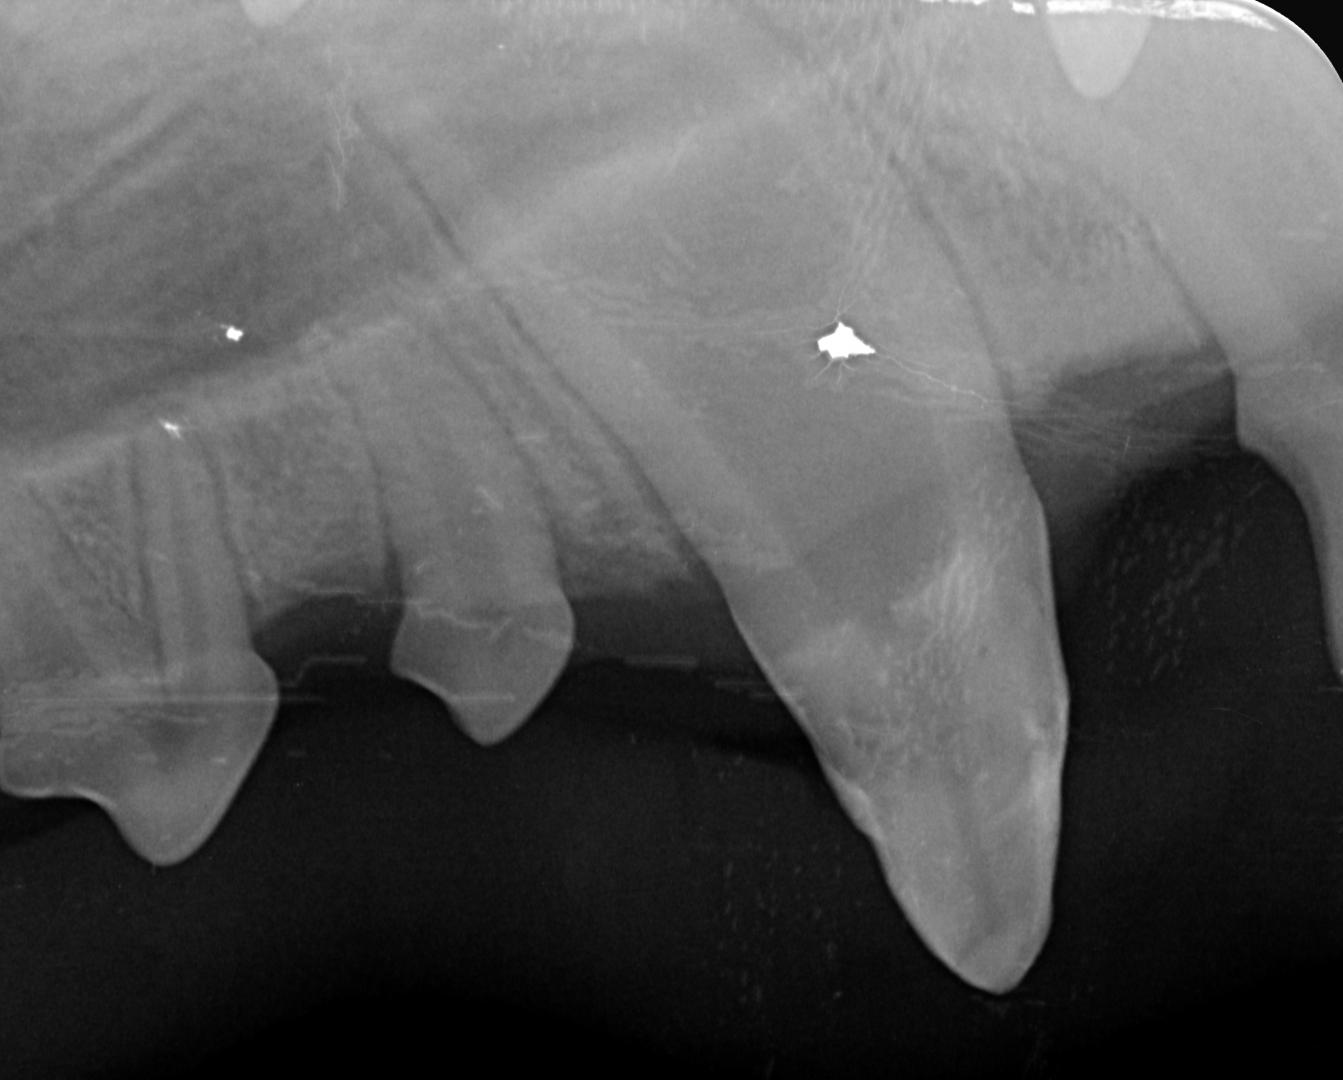

...et voilà le travail....!

Des trous comblés, une dent lissée, pour une fonctionnalité restaurée et une dent qui peut continuer à évoluer!

Des contrôles seront effectués pour s'assurer que la dent continue à évoluer normalement, et que la résine tient (avec un chiot qui a une forte tendance à mâchouiller tout ce qui lui passe entre les dents, rien n'est garanti!) l'objectif étant de permettre à Alphonse de conserver son beau sourire, et un croc fonctionnel!